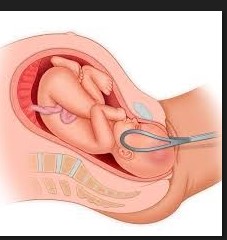

– Akenshi bisaba ubufasha bwihariye: kubyara hakoreshejwe ibikoresho (forceps/vacuum) cyangwa kubagwa (cesarean section).

Ingaruka

Igihe umwana atari mu mwanya mwiza mu nda ya nyina, bituma kubyara bigorana, bishobora gutera umwana kubura umwuka cyangwa umubyeyi kuva cyane. Akenshi bisaba ubufasha bwa muganga, harimo kubyara hakoreshejwe ibikoresho byihariye cyangwa kubagwa (cesarean section).